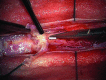

Adhesive arachnoiditis is a rare condition, often complicated by syringomyelia. This pathologic entity is usually associated with prior spinal surgery, spinal inflammation or infection, and hemorrhage. The usual symptoms of arachnoiditis are pain, paresthesia, and weakness of the low extremities due to the nerve entrapment. A few cases have had no obvious etiology. Previous studies have reported one family with multiple cases of adhesive arachnoiditis. We report a second family of Belgian origin with multiple cases of arachnoiditis and secondary syringomyelia in the affected individuals.